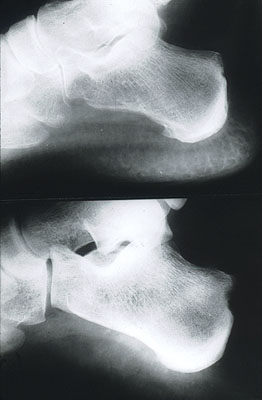

Arthritis Mutilans In A Patient With Psoriasis - Turner

He was not taking any medication at the time of presentation. Psoriatic arthritis (PsA) is a seronegative, inflamma-tory arthropathy occurring in 5% to 42% of patients Gaffar : Psoriatic Arthritis Mutilans : pp. 46–50 Figure 4. ... Retrieve Full Source